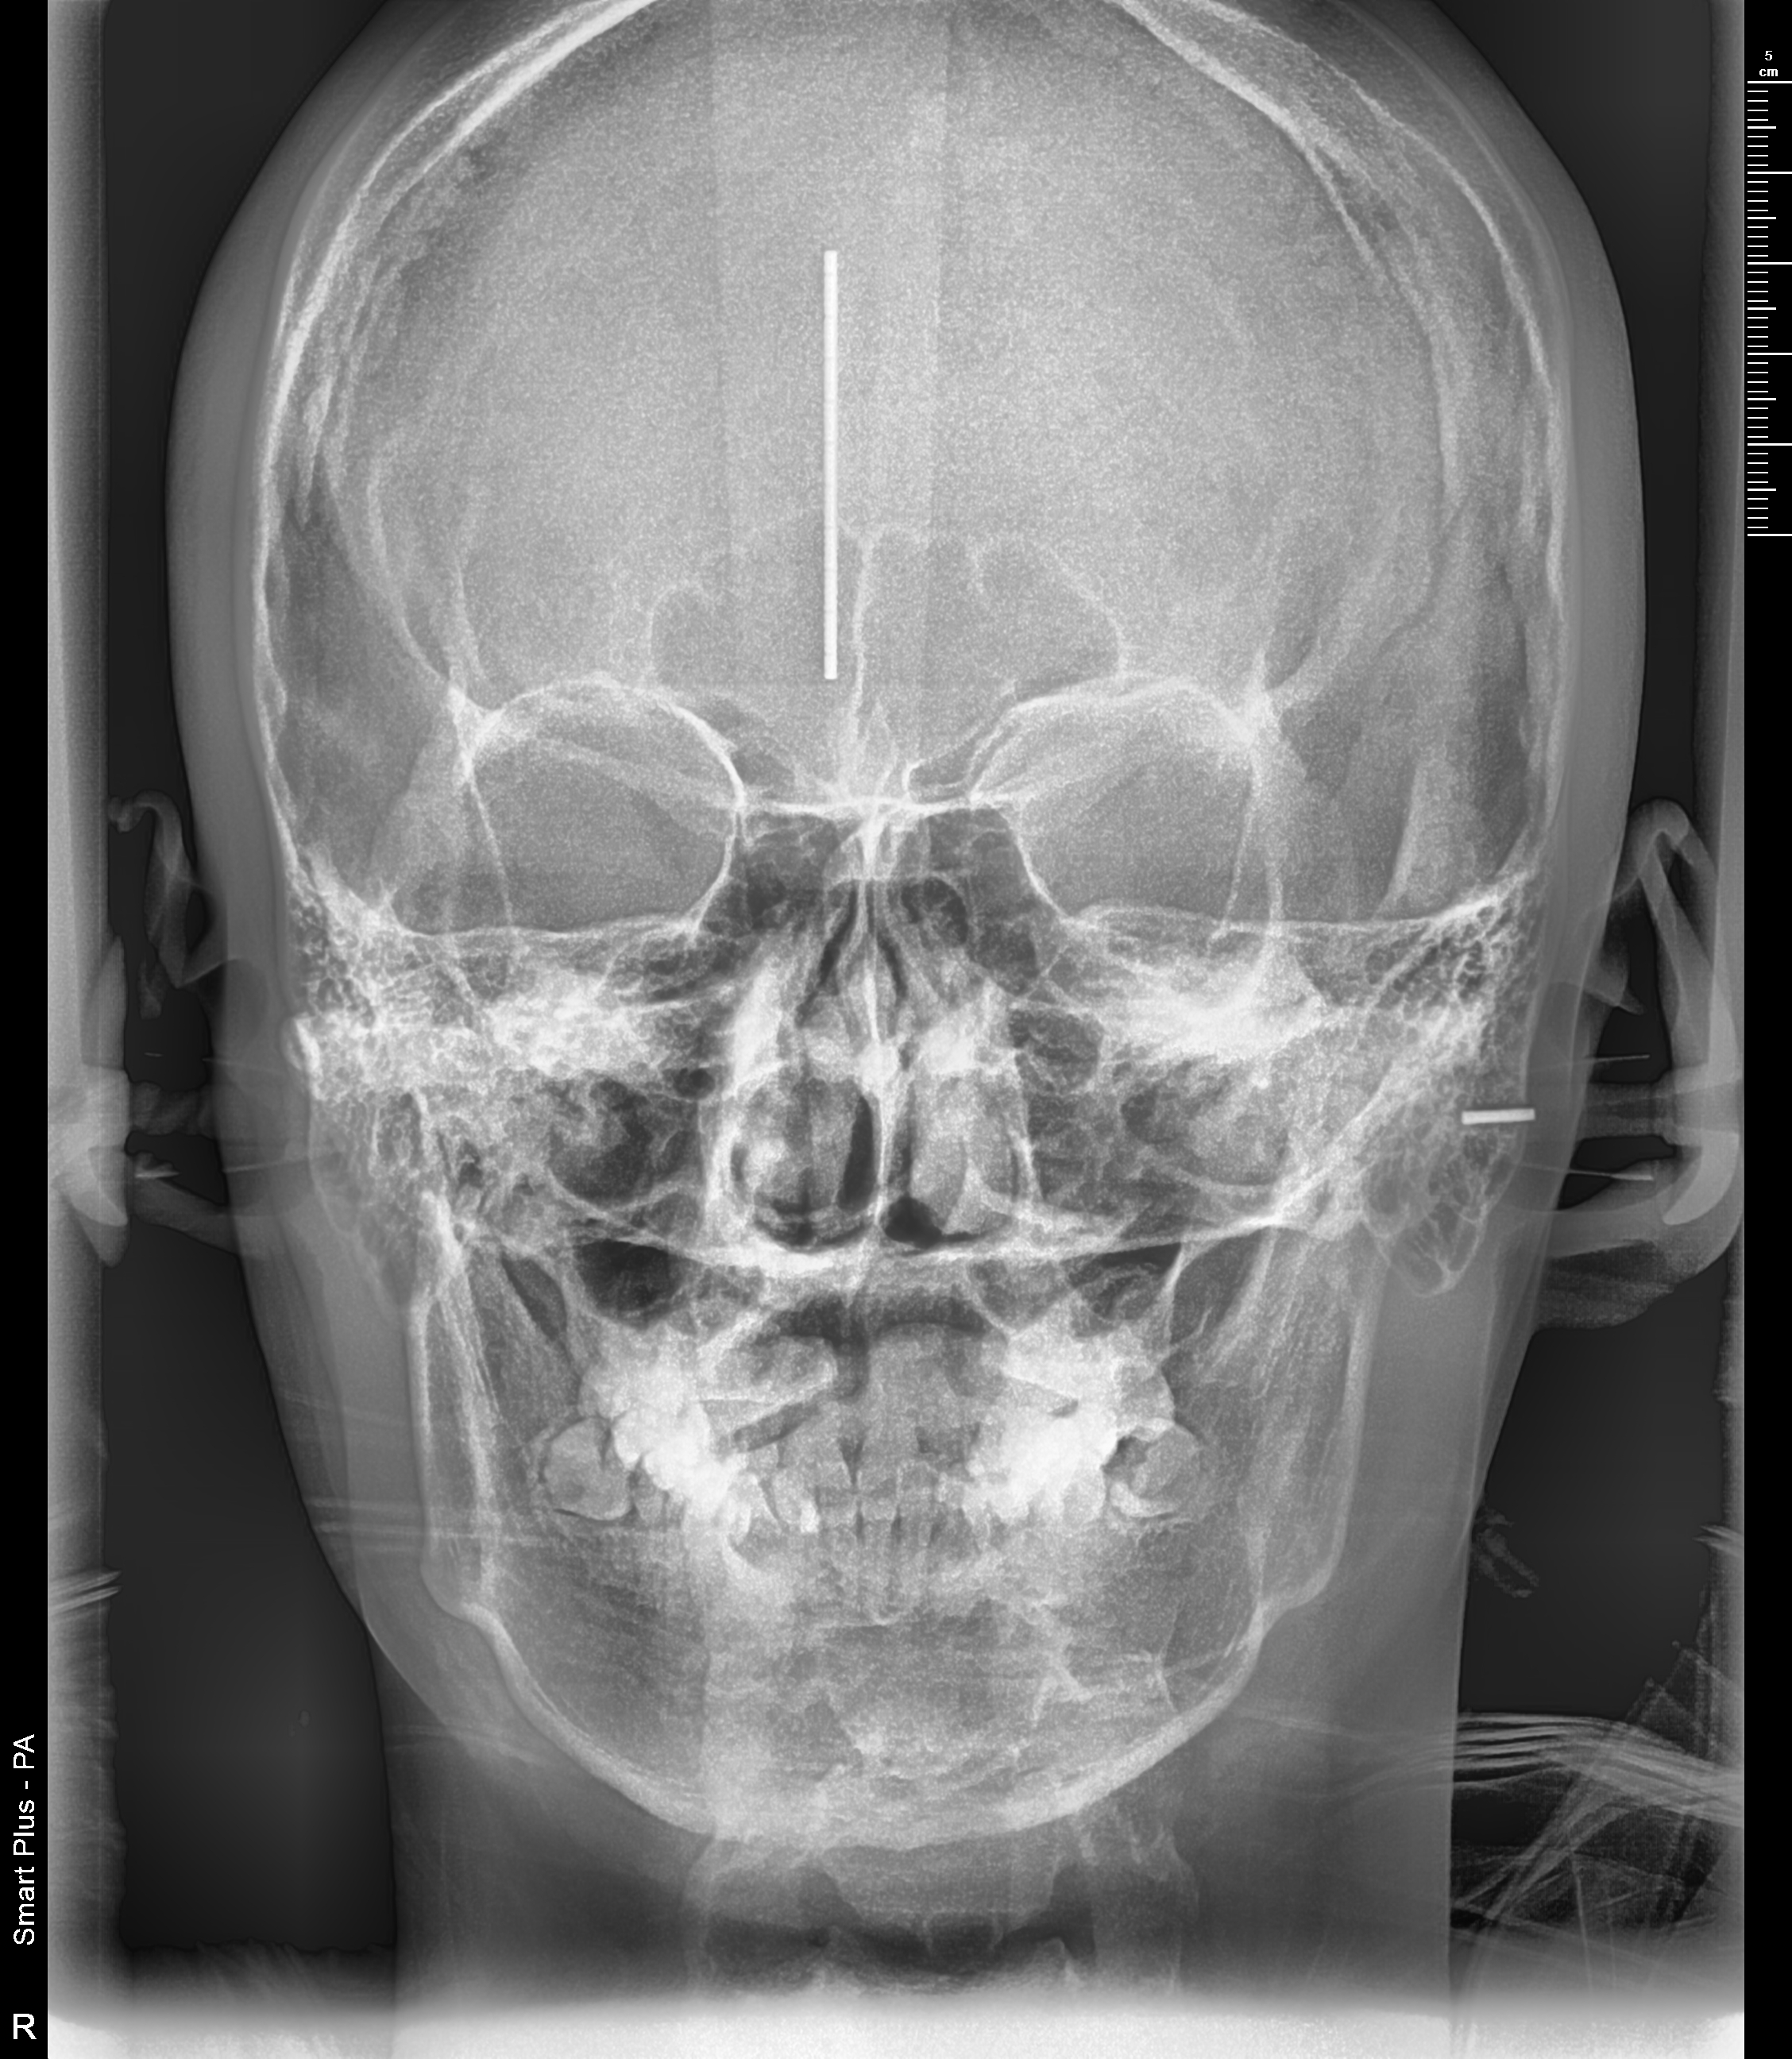

전체적인 치아상태 및 배열 안면윤곽 상태 등 정밀검사를 실시하였으며 아들이 고등학생이어서 성장판 검사는 별도로 하지 않았습니다.

정밀검사비용은 150,000원이 들었으며 전체교정비용은 590만 원으로 결정이 되었습니다. 치료방법에 따라 다르기 때문에 참고만 하시길 바랍니다.

● 검사결과 내용

치아뿌리상태는 좋고 어금니 가위교합(3개월정도)을 먼저 하고 어느 정도 진행이 되면 전체브라켓을 설치 후 과개교합(2개월정도) 교정을 실시한후 2차 정밀검사를 하고 발치여부를 판단하기로 하였습니다.

저는 상담 시 되도록이면 발치는 하지 않는 방향으로 한다고 말씀드렸고 다행히 2차 정밀검사 마친 후 발치 없이 전체교정을 시작할 수 있었습니다.

▼ 1차 정밀 검사 X-RAY

▼ 치아상태 및 얼굴 각도 치아 치수확인